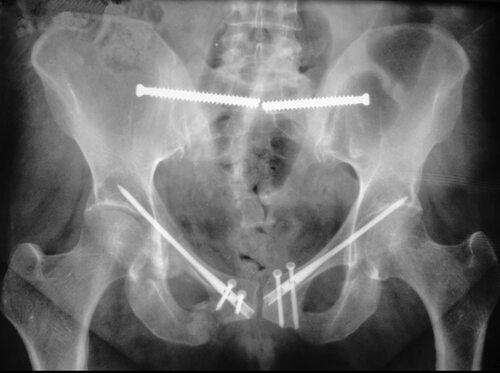

Перелом кости таза является серьезным повреждением, которое может возникнуть в результате аварий, падений или других травматических ситуаций. Этот тип переломов обычно требует немедленной медицинской помощи и длительного периода восстановления.

Фото перелома кости таза

В данной статье мы предлагаем вам ознакомиться с некоторыми фотографиями, иллюстрирующими различные типы переломов кости таза. Однако, предупреждаем, что содержание может быть шокирующим, поэтому если вы не готовы видеть изображения с травмами, рекомендуем воздержаться от просмотра.